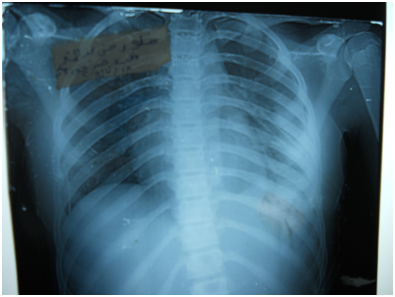

A 17-year-old girl (170cm, 60kg) presented to the emergency department with dyspnea and chest pain after a penetrating stab wound to the chest in the left sixth intercostal space mid-clavicular line, which happened 2hours earlier. Upon physical examination, Pulse was 96 beats per minute and blood pressure was 110/70mmHg, diminished air entry was noticed on the left side of chest. Chest x-ray revealed left hydropneumothorax. Tube thoracostomy was performed left intercostals tube was inserted for drainage. Post-insertion chest x-ray revealed no improvement in the picture of air fluid level (Figure 1) (Figure 2) which was further evaluated by CT that showed fluid collection posteriorly and air anteriorly (Figure 3) (Figure 4). Two days later patient had fever with vomiting and leucocytosis. The nature of the drain from the intercostal tube becomes serosangenous and less hemorrhagic with change in color associated with food. Methylene blue dye (1% concentration) taken orally by the patient was detected in the drain of the intercostal tube two minutes after ingestion (Figure 5). Oral contrast chest x-ray was done, two shots were taken one on swallowing gastrographin, it showed the esophagus outlined without any leakage (Figure 6A). The other shot taken two minutes after oral administration of gastrographin in trendlenberg position, the contrast outlined a track passing from the fundus of the stomach to the left pleural cavity and to the intercostals tube (Figures 6B) (Figure 6C). Laparotomy was performed via midline incision and findings were confirmed. It showed a 3cm orifice of the left copula of the diaphragm with a tear in the gastric fundus which was closed in two layers and the diaphragmatic tear was closed directly with continuous sutures. Two weeks later patient complicated by left empyema with thickened pleura. Thoracotomy was done for complete evacuation of pus and decortication. The patient fully recovered and was discharged 8days after thoracotomy.

Figure 1 Post intercostals tube insertion chest X-ray.

Figure 2 Second day post intercostals tube insertion chest X-ray.